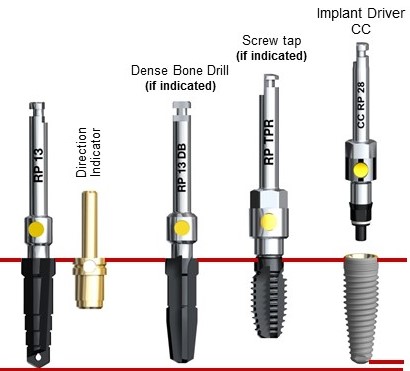

— другие компании, например Dentsply Sirona Implants (изначально Friadent), Dentium и т. д., наоборот, разработали такой дизайн имплантов, который позволяет использовать их в максимально широком диапазоне клинических случаев. Иначе говоря, как первый случай, так и второй, можно решить одним видом имплантов и одним хирургическим протоколом, что, как мне кажется, удобнее и логичнее.

Но, допустим, вы взяли ту же систему Dentsply Astratech, благо у нее есть импланты диаметром 3.0 мм, и спокойно поставили имплантат такого диаметра в область 41 зуба. Через какое-то время, когда имплантат интегрировался, пациент пошел к ортопеду и, как ни странно, захотел коронку на оксид-циркониевом каркасе. Ну, или цельнокерамическую коронку — эстетически значимая зона же. Ортопед судорожно роется в каталогах и с ужасом понимает, что на импланты Astratech диаметром 3.0 мм нет супраструктур для изготовления цельнокерамических коронок, в каталоге только прямые и угловые стандартные абатменты! Что делать?

Как говорит мой коллега Сергей Балабанников, цивилизованными методами эту проблему не решить. Нецивилизованными методами изготовить и зафиксировать цельнокерамическую коронку на имплантат диаметром 3.0 мм конечно можно, но кто даст гарантии, что такая работа долго простоит, и с ней не будет никаких проблем?

Вот вам еще одно ограничение — количество и варианты супраструктур, которые возможно установить на один имплантат. Чем больше супраструктур (протетических компонентов) — тем выше вариабельность и диапазон клинических случаев, при которых можно использовать данную имплантационную систему.